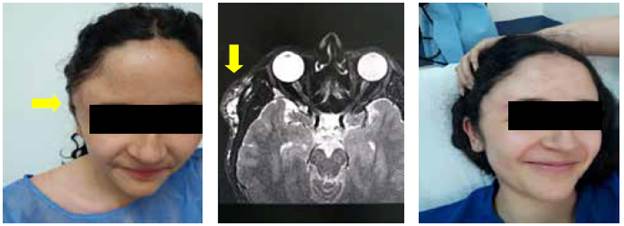

Las malformaciones linfáticas, que la literatura denomina higroma quístico o linfagioma, se diagnosticaron en 12,5 % de casos, la mayoría en niños pequeños, y su localización más frecuente es la cabeza y el cuello (figura 1). Tienen mayor recidiva con manejo quirúrgico y mejores resultados con los procedimientos percutáneos 10 (figura 2).

En este estudio las malformaciones arterio-venosas fueron la segunda anomalía vascular en frecuencia de presentación (33,3 %), y se manifestaron en forma de masa pulsátil (figura 3). Estas malformaciones hacen referencia a trayectos fistulosos de alta velocidad y baja resistencia, que comunican de forma anormal arterias con venas 11,12.